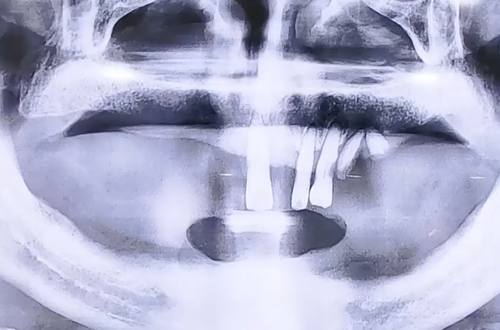

BEFORE

아랫니는 모두 발치하셨고, 윗니에 건강하지 않은 치아 몇개인 상태로 전체 임플란트를 진행하여 치아 기능을 회복시켜 드린 환자분의 사례입니다.

이 경우 본래 끼워준 틀니가 양옆과 앞뒤 모든 방향으로 흔들림이 없도록 최소 4개 이상의 임플란트를 식립하는데, 환자분은 아랫니를 발치한지 오래되어 잇몸뼈가 퇴축된 상태로, 임플란트를 심을 공간이 부족해 어쩔 수 없이 2개만으로 진행하기로 결정하고 치료가 시작되었습니다.